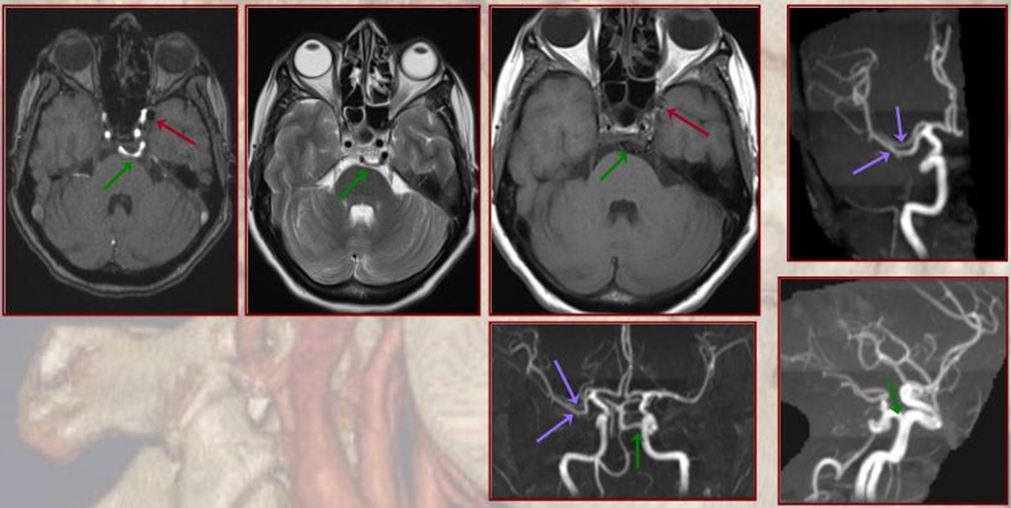

In the case below, the trigeminal artery itself is associated with a large aneurysm. Is it intradural or extradural?

Below is a right PCA (P2) segment embolic occlusion. This is an artery to artery embolus from a diseased right cervical carotid (no arrows needed), via the trigeminal (dashed arrow), into the right P2 (arrow). The anatomy solves the riddle — left PCOM is fetal (no arrows needed), thus left P1 is hypoplastic and embolus of that size would not go there. it also could not have come from the verts because the basilar below trigeminal is hypoplastic as well (arrowhead) — in fact this was originally considered a basilar occlusion. However, clinical presentation was not consistent with that location and basilar hypoplasia below trigeminal is common. Excellent clinical correlation here.